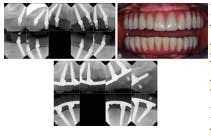

In the All-on-Four concept, four implants are used to support an acrylic, screw-retained provisional prosthesis, then a final prosthesis about four months later. Although this method uses only four implants, two of them are placed distally tilted in areas where bone height, nerve proximity, or other conditions make it impossible to place the implant axially. This tilting allows the placement of longer implants that have good anchorage in the best positions for prosthetic support. Previously, standard practice called for dental implants of at least 4.0 mm in diameter. For tilted implants in particular, this was considered the smallest diameter that could guarantee sufficient anchorage. The NobelActive implant, introduced in 2008, made it possible to use a 3.5 mm diameter implant for patients with atrophic jaws. Featuring tapering, a variable thread, and an inward tapered collar, this implant offers self-drilling capacity and bone compression qualities. High torque values can be reached, giving the implant high initial stability.RELATED |Fluoride treatment of synthetic biomaterial assists dental bone regeneration Prior studies have found that failed implants using the All-in-Four method were a result of soft bone and lower insertion torque values. The combination of a 3.5 mm diameter implant and the All-on-Four technique brings new treatment possibilities to patients with severe bone deficiencies.Full text of the article, “A New Approach to the All-on-Four Treatment Concept Using Narrow Platform NobelActive Implants,” Journal of Oral Implantology, Vol. 39, No.3, 2013, is available here.About Journal of Oral Implantology The Journal of Oral Implantology is the official publication of the American Academy of Implant Dentistry and of the American Academy of Implant Prosthodontics. It is dedicated to providing valuable information to general dentists, oral surgeons, prosthodontists, periodontists, scientists, clinicians, laboratory owners, and technicians, manufacturers, and educators. The JOI distinguishes itself as the first and oldest journal in the world devoted exclusively to implant dentistry. For more information about the journal or society, please visit their website.